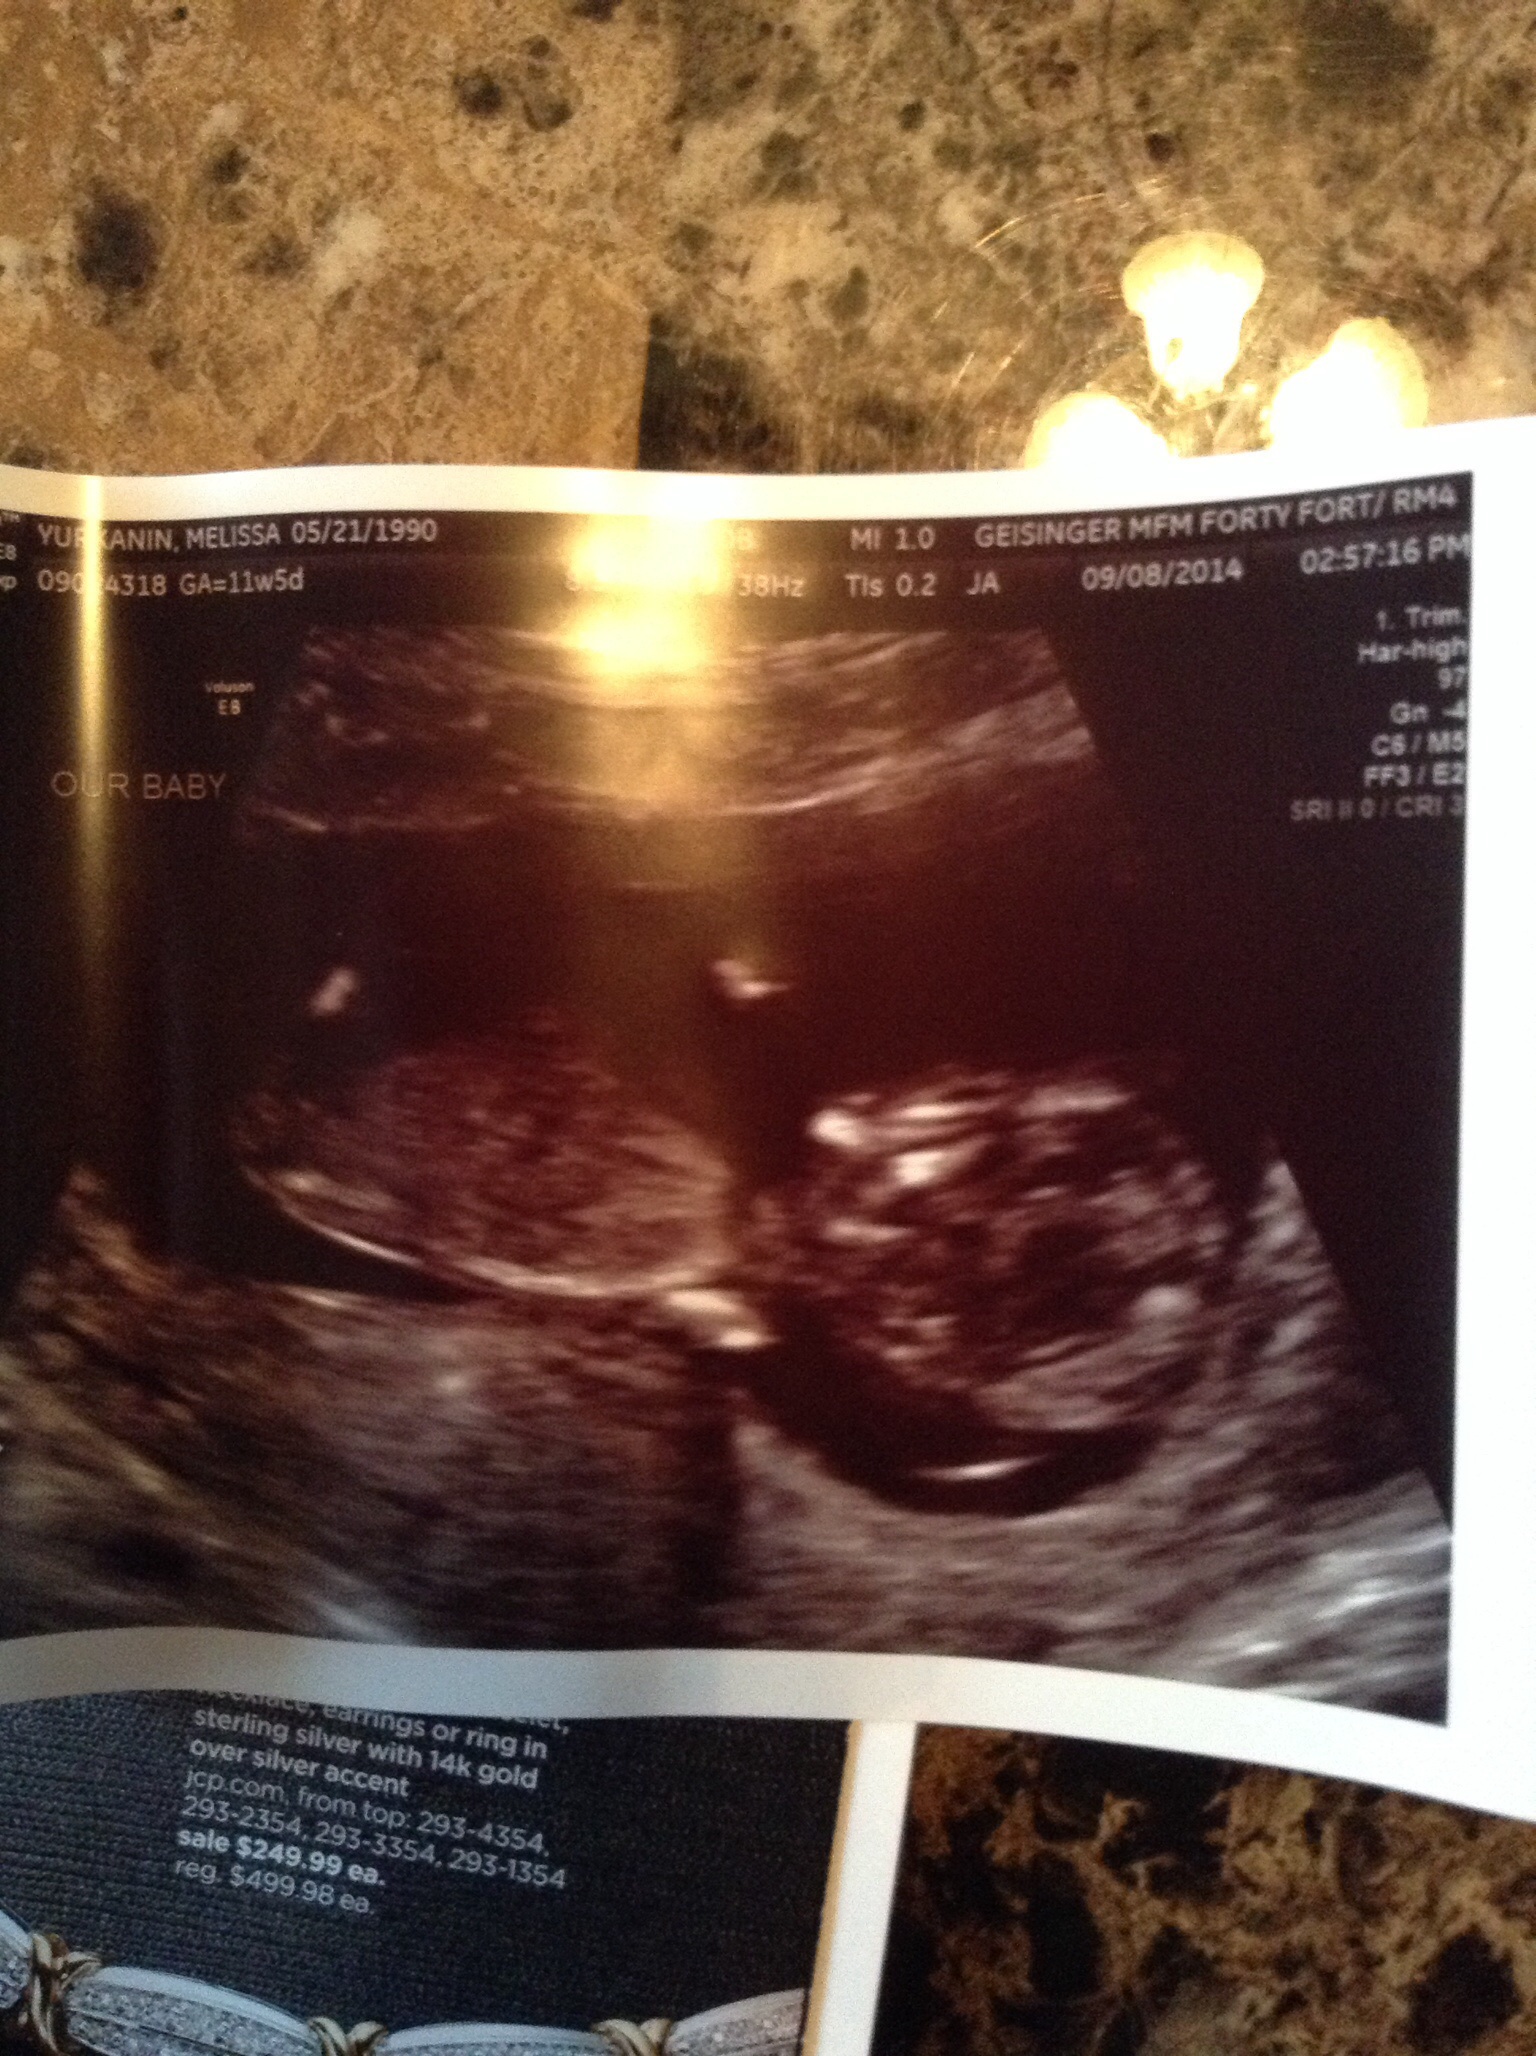

Measuring 12w 5d but only 11w 5d.